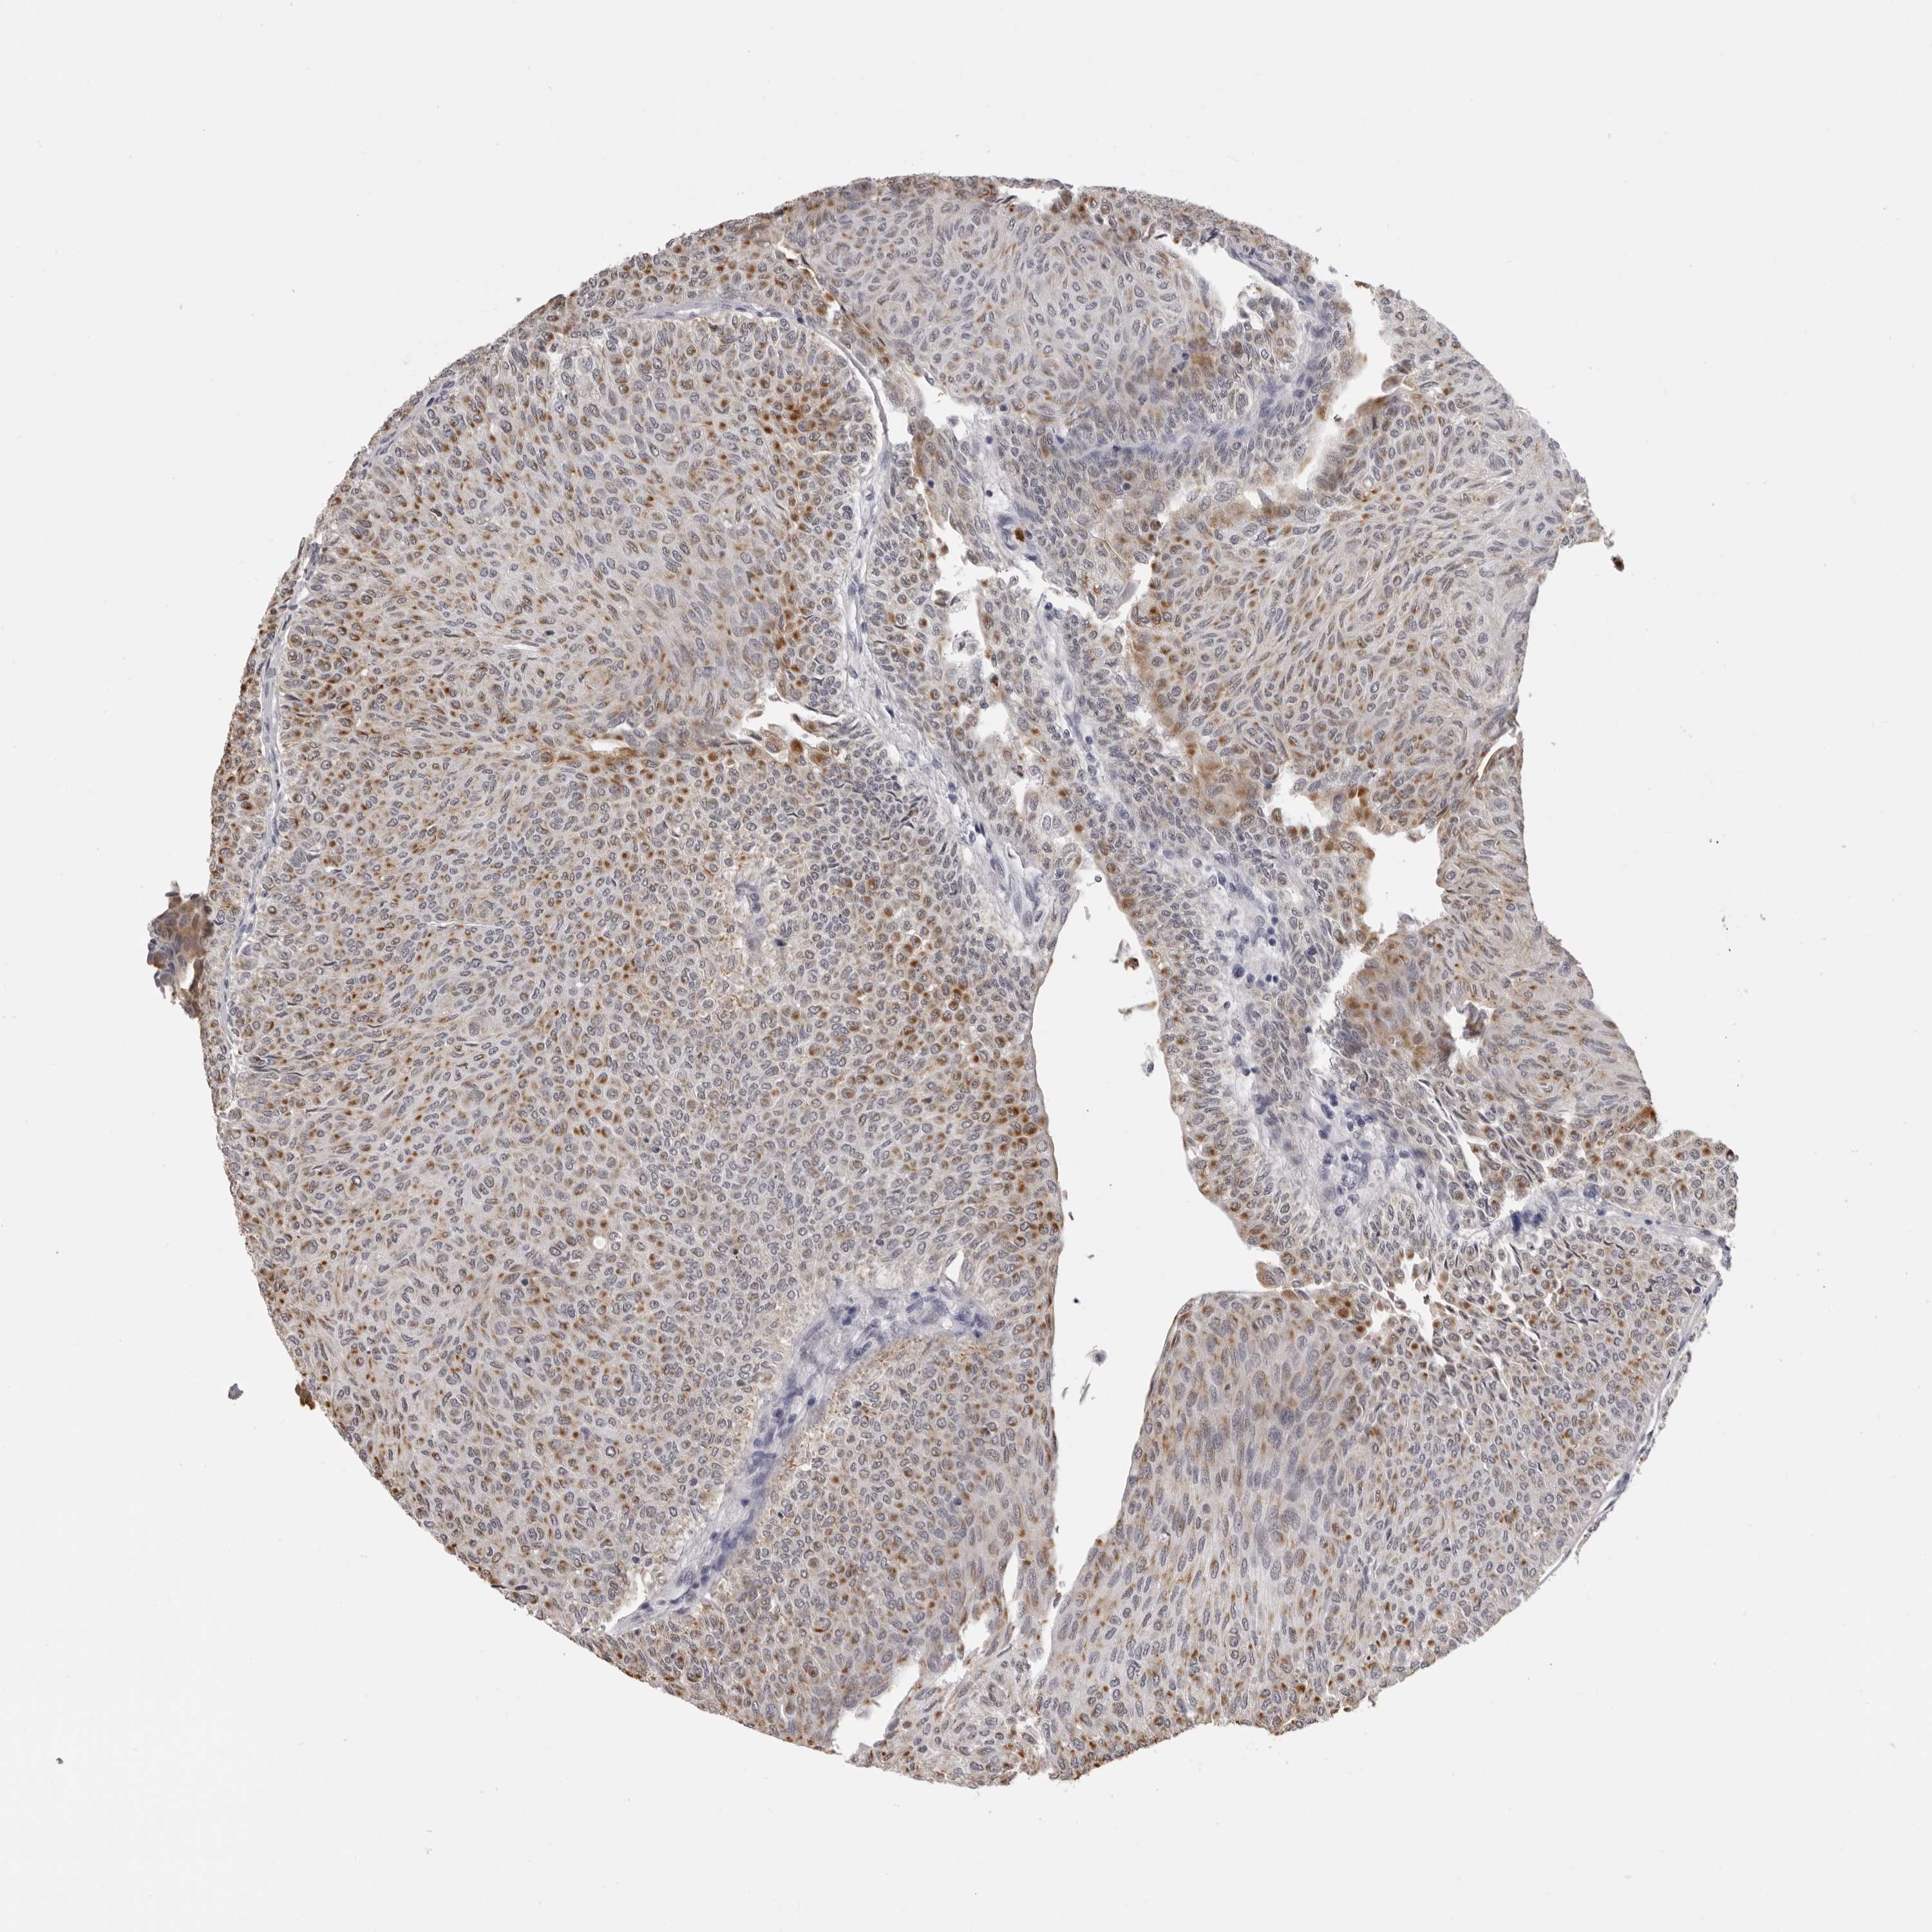

UROTHELIAL CANCER - Protein expressioni

A mouse-over function shows sample information and annotation data. Click on an image to view it in a full screen mode. Samples can be filtered based on level of antibody staining by selecting one or several of the following categories: high, medium, low and not detected. The assay and annotation is described here.

Note that samples used for immunohistochemistry by the Human Protein Atlas do not correspond to samples in the TCGA dataset.

Antibody stainingi

Antibody staining in the annotated cell types in the current human tissue is reported as not detected, low, medium, or high, based on conventional immunohistochemistry profiling in selected tissues. This score is based on the combination of the staining intensity and fraction of stained cells.

Each image is clickable and will lead to virtual microscopy that enables deeper exploration of all samples and also displays staining intensity scores, fraction scores and subcellular localization as well as patient and tissue information for each sample.

Antibody CAB025657

Staining

High

Medium

Low

Not detected

Intensity

Strong

Moderate

Weak

Negative

Quantity

>75%

75%-25%

<25%

None

Location

Nuclear

Cytoplasmic/membranous

Cytoplasmic/membranous,nuclear

Urothelial carcinoma, Low grade

Urothelial carcinoma, High grade